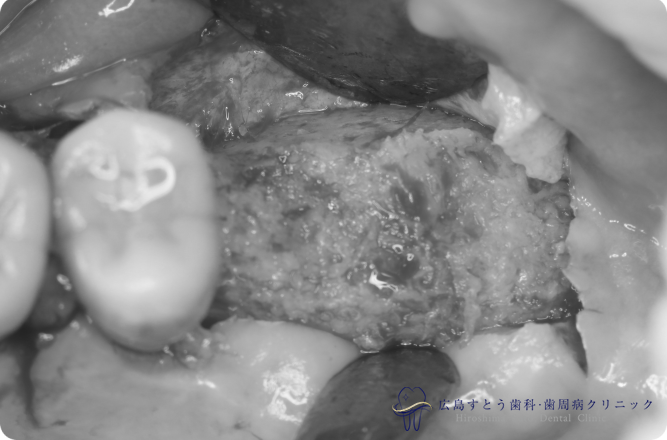

術中(手術中の写真)

手術中の状態:骨移植前

右下の手術中の状態:骨移植前

右下の手術中の状態:骨移植後